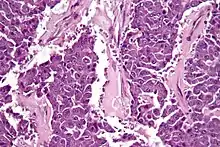

| Micrograph of an acinar cell carcinoma of the pancreas. H&E stain. | |

Histomorphologically, the tumour resembles the cells of the pancreatic acini and, typically, have moderate granular cytoplasm that stain with both PAS and PASD.[4]

Light microscopy of an acinar cell carcinoma biopsy typically shows granular appearance.[6] Immunohistochemistry is usually positive for trypsin, chymotrypsin and lipase.[6] On genetic testing, altered genes/proteins are typically found for p53, SMAD4, APC, ARID1A and GNAS.[6]